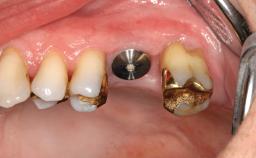

A 31-year-old man presented to our clinic 30 days after a motor vehicle accident in which he had suffered a dentoalveolar fracture in the anterior maxilla, including avulsion of teeth 12 and 11 and luxation of tooth 21. He was first treated on the night of the accident in a small city hospital with no oral and maxillofacial surgeon on the staff. A wired retention had been applied and the teeth repositioned to the best of the clinicians’ abilities. When he first presented to our care, the patient showed extrusion of teeth 12 and 11 associated with gingival recession due to bone loss in the anterior maxilla, and the stainless steel wires were still present.